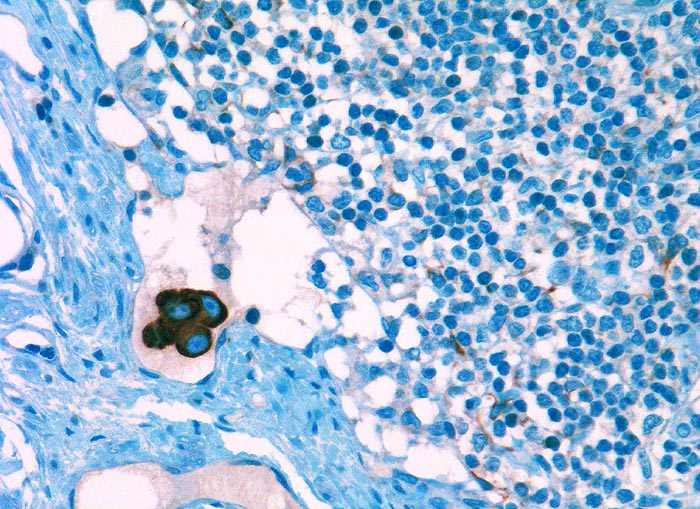

l/ Panzytokeratin (CK22/Lu-5)

Panzytokeratin (CK22/Lu-5)

Anfärbung:

Zytoplasma positiv.

Reaktion im Normalgewebe:

CK22 und Lu-5 repräsentieren Zytokeratingemische, welche einen Grossteil normaler und neoplastischer Epithelzellen anfärben.

Reaktion in Neoplasien:

Die meisten Karzinome und vereinzelte Sarkome reagieren positiv mit diesen Panzytokeratinen. CK22 ist etwas sensitiver und spezifischer als Lu-5. Entdifferenzierte oder sarkomatoide Karzinome können die Positivität für Zytokeratine verlieren.

Diagnostischer Nutzen:

Suchantikörper zur Abgrenzung von Karzinomen von Lymphomen, Sarkomen und malignen Melanomen. Identifikation von Karzinommikrometastasen in Lymphknoten.